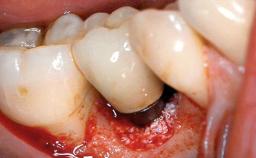

Peri-implantitis Resulting in Bisphosphonate-related Osteonecrosis of the Jaw

A 82-year-old female patient was referred to the Department of Oral Surgery and Stomatology at the University of Bern, Switzerland, for further diagnosis and treatment of growing discomfort in the right mandible (implant 45) and left maxilla (implant 23). The patient had had implants of various types inserted in the mandible and maxilla over the course of the previous three decades (in the 1980s and 1990s). The patient had received removable partial dentures on implants in the maxilla and on natural teeth in the mandible. The implants in the posterior right mandible had been restored with two splinted single crowns. The lower partial denture was not well tolerated by the patient and therefore had not been worn for over ten years. After insertion of the implants, there had been no complications for many years, but implants 45 and 46 as well as 23 had begun to exhibit signs of peri-implantitis with limited bone loss several years previously. The infection had been treated by the private practitioner, and bone loss around the three implants had not progressed until about half a year previously.